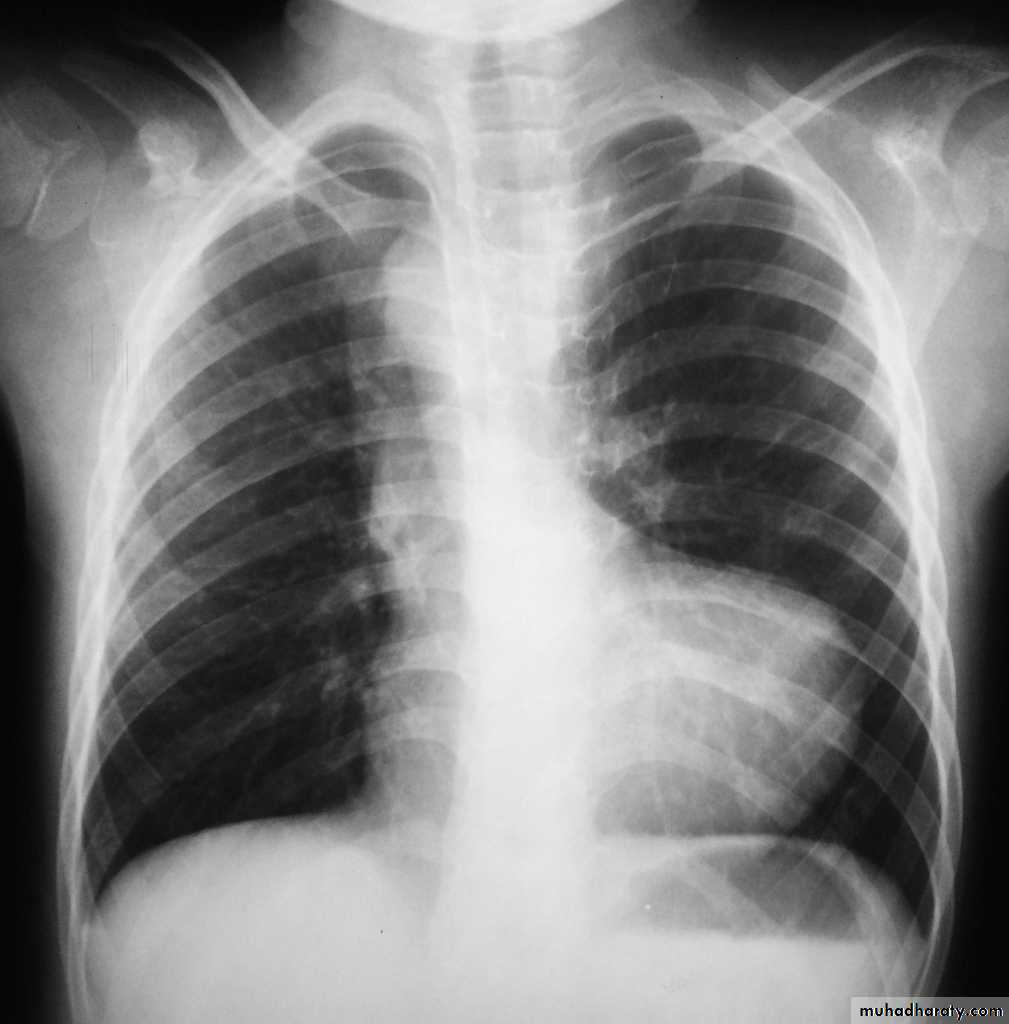

Published on behalf of the European Society of Cardiology. All rights reserved. © The Author 2014. For permissions please email: journals.permissions@oup.comPDA: Investigations: CXR

LV & LA dilatationProminent main pulmonary artery

Plethoric lungs (increased pulmonary vascular markings: arterial and venous)

Prominent aorta

In older patients: the ductus may be calcified